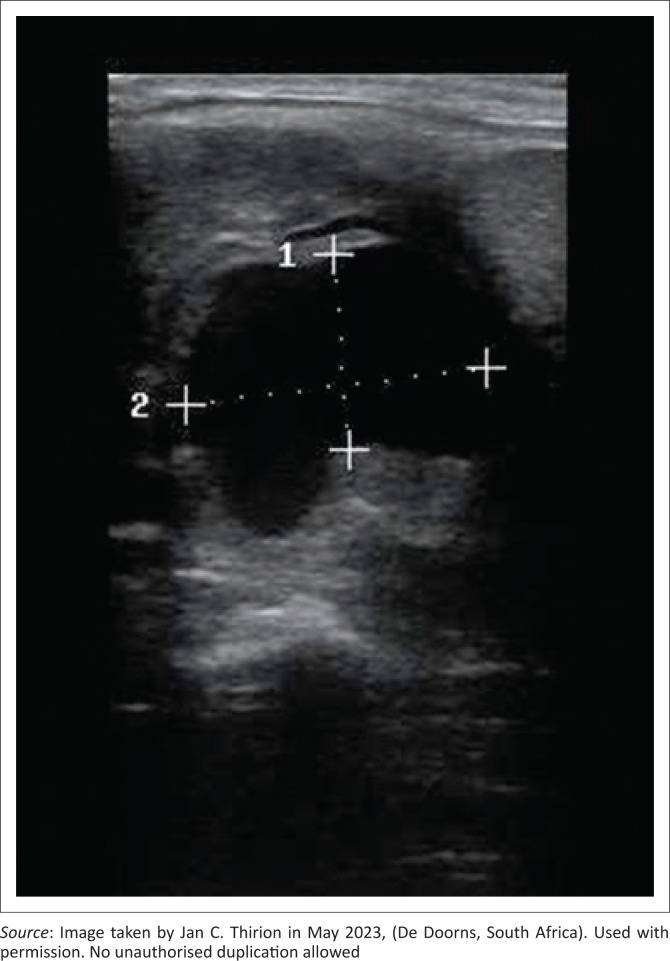

Patient presentation:  A 19-year-old male presented to a rural primary health care clinic in the Western Cape of South Africa with a 3-week history of left-sided neck swelling and recent odynophagia. Physical examination revealed a firm, pulsatile mass with an audible bruit.

Management and outcome:  Formal imaging was unavailable for several months, delaying surgical advice. However, the clinic's newly procured mobile ultrasound allowed for PoCUS, which identified a pulsatile vascular lesion consistent with a carotid pseudoaneurysm. Computed tomography angiography confirmed the diagnosis, and the patient was referred for tertiary care where the lesion was repaired. He had vasculitis on histology and exhibited inconclusive features of a connective tissue disorder, but a definitive cause was not found. Despite multiple attempts, he could not be contacted for follow-up.